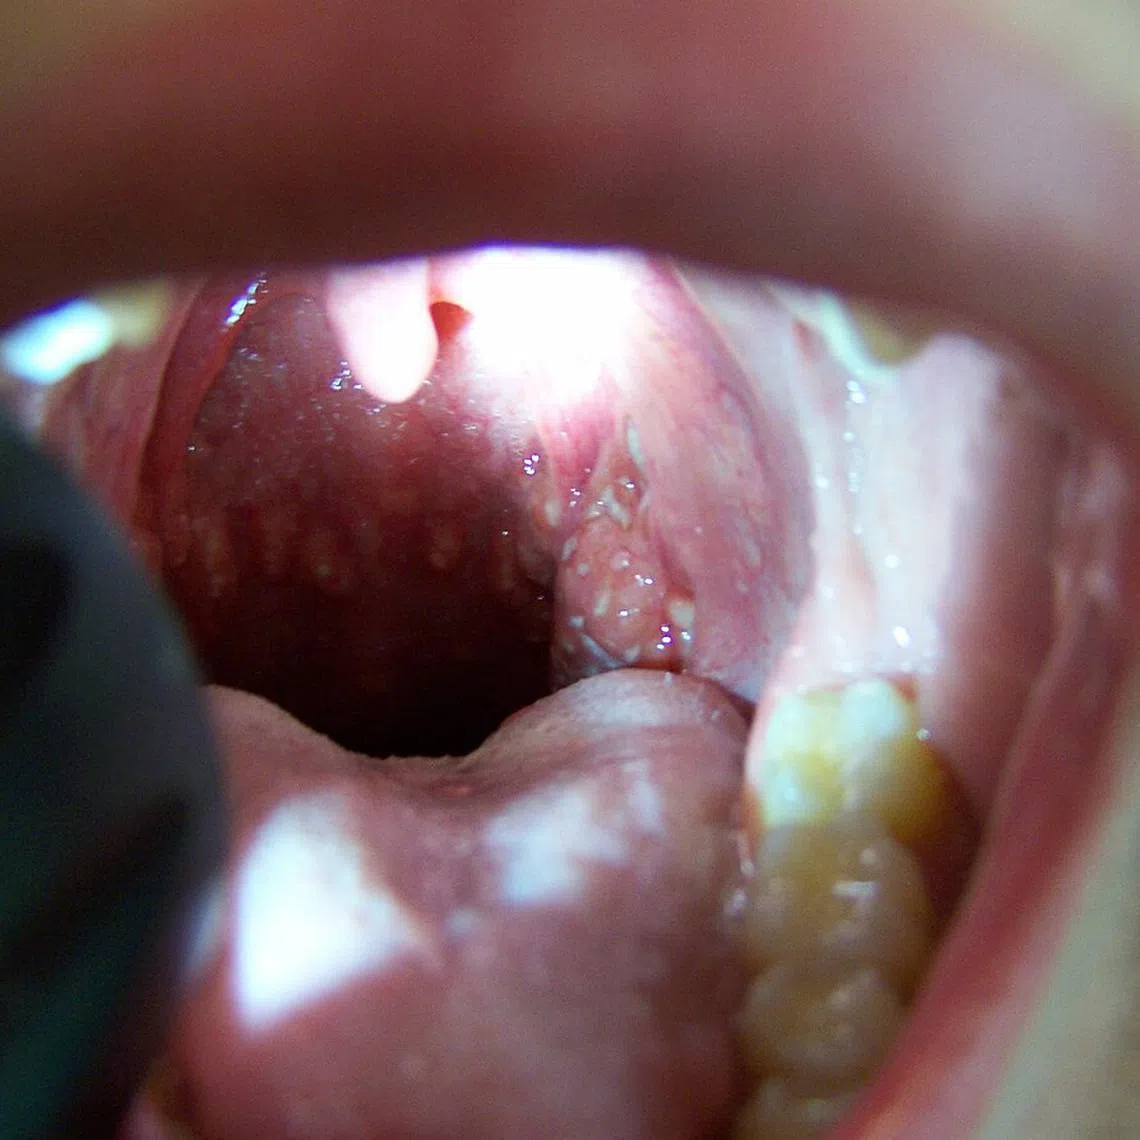

Young at heart? Catching a childhood disease as an adult is no fun